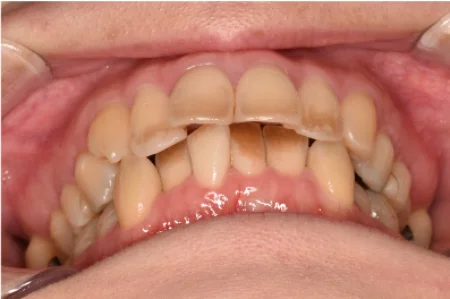

一般歯科 2023.0430代女性「上の前歯に熱いものがしみる」虫歯を取り除いて白いペースト状の材料「コンポジットレジン」で修復し、歯周病の治療も並行して進めて口の中全体を健康にした症例